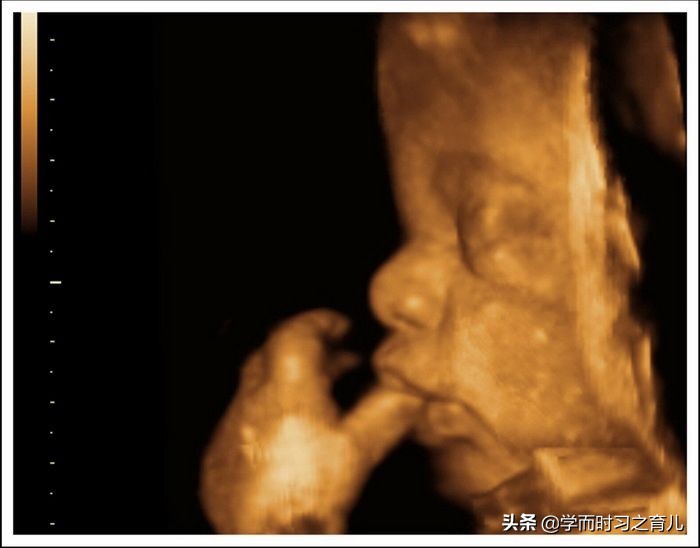

3、宝宝太懒

除了以上两种情况,四维彩超不顺利还有可能是胎儿太懒的原因,往往医生检查完这一面了,胎宝宝还不翻身,懒得只知道动动胳膊,踢踢腿,但医生需要比较全方位的检查胎儿,因此这种情况也是不太顺利的。

有些懒宝宝还好,在准妈妈运动一下,吃点东西以后还会乖乖翻个身动一下,可有些胎宝宝不管准妈妈怎么运动,他(她)就是不肯稍微动一下,这也是懒到家了。如果胎宝宝一天都不翻身,那准妈妈只有隔天或者改天再来检查了。